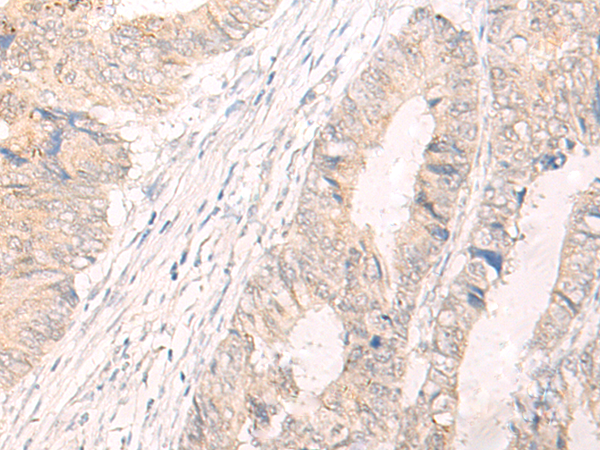

分类: 科研抗体货号: P06448别名: IL25; IL27; SF20; IL27w; C19orf10; R33729_1; EUROIMAGE1875335应用: WB,IHC反应种属: Human, Mouse